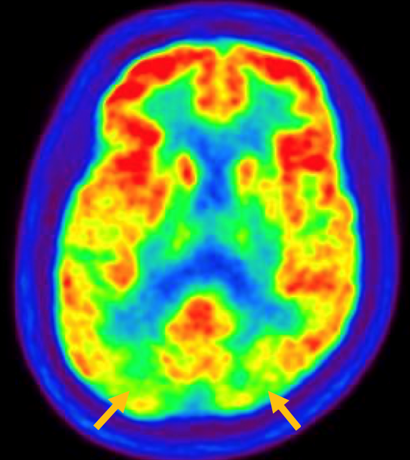

피질 기저핵 변성은 비대칭 증상을 두드러지게 보인다는 점에서 파킨슨병과 비슷합니다. 그러나 파킨슨병과 비교해 보았을 때 양측의 차이가 아주 심하게 나타난다는 특징이 있습니다. 질병 초기에 한쪽 손으로 동작을 하거나 계획된 행동을 하는 기능이 현저하게 떨어집니다. 간단한 손가락 모양도 따라 하지 못하는 현상을 보입니다. 또한 의지와 상관없이 제멋대로 움직이는 통제불능 손이 나타날 수 있습니다. 체위 떨림, 경축, 운동 완만과 같은 파킨슨병에서 볼 수 있는 증상들은 피질 기저핵 변성에서도 관찰될 수 있습니다. 또한 집중력 장애, 수행 장애, 이름 대기나 언어의 유창성이 떨어지는 등 전두엽 및 두정엽과 관련된 인지 장애가 나타납니다. 피질 기저핵 변성은 뇌 자기공명영상(MRI)에서 증상의 반대쪽 전두두정엽의 위축 소견이 특징적으로 나타납니다. 뇌포도당 양전자 단층촬영(PET)에서도 전두엽, 뇌기저핵에 비대칭적인 대사 저하의 소견이 보입니다.

[피질기저핵 변성 환자의 뇌포도당 양전자 단층촬영에서 확인되는 비대칭적인 대사 기능 저하]